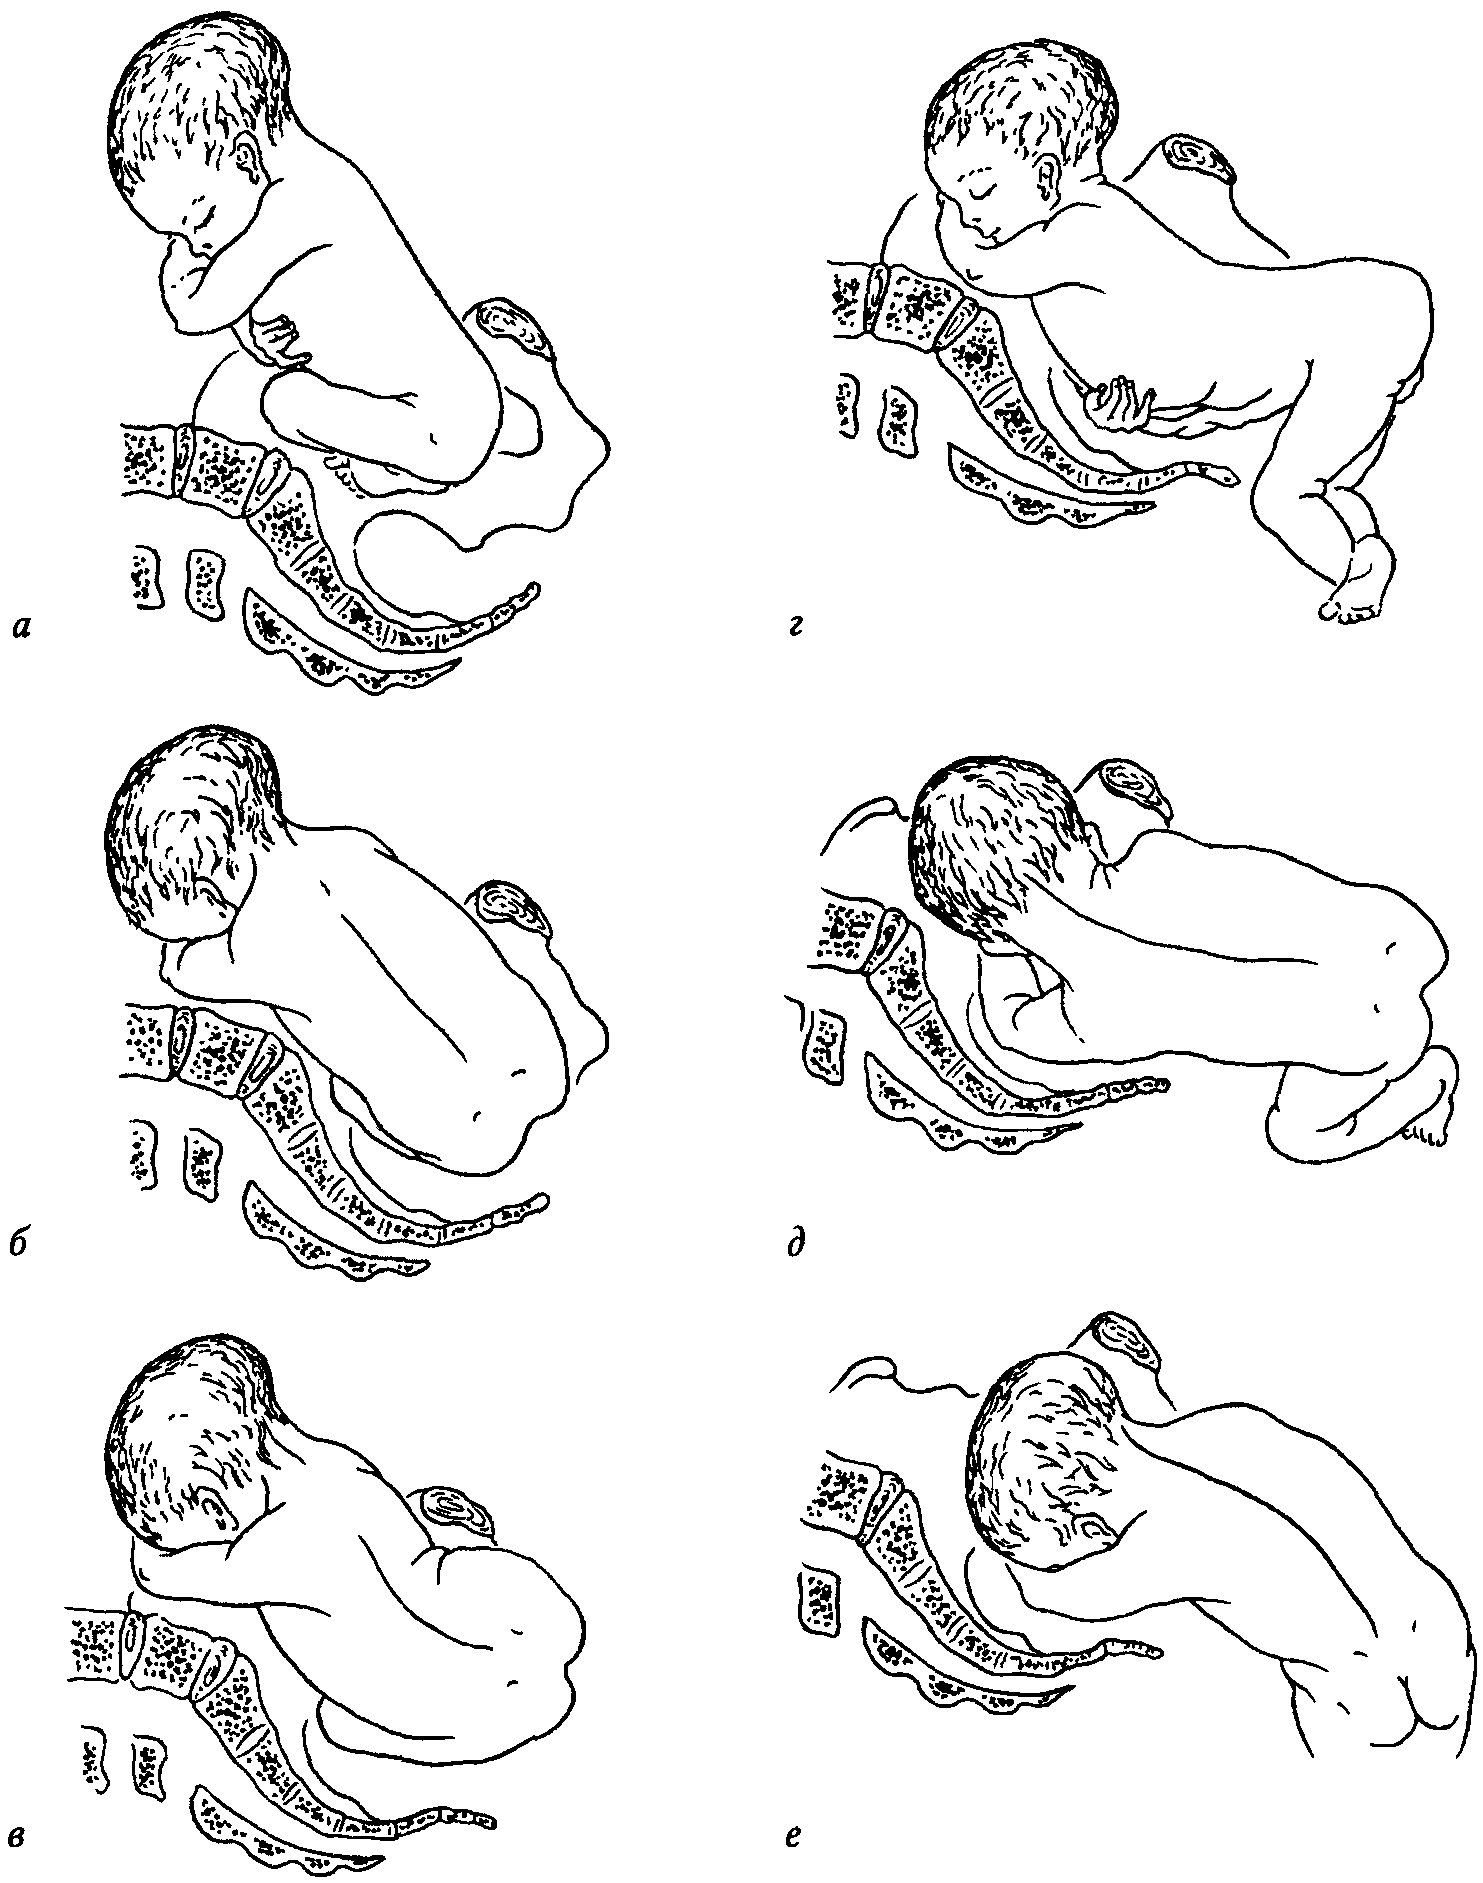

Биомеханизм родов в переднеголовном предлежании

Биомеханизм родов таблица

Биомеханизм родов таблица

Первый момент биомеханизма родов при тазовом предлежании